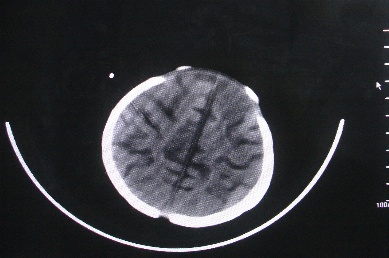

以下是引用余辉在2007-4-30 16:36:00的发言:[br]呵呵,图片不行啊,双肺弥漫斑片状影。右肺门增大,结构模糊。左侧脑室前部室管膜下可见团块状高密度影,周围有低密度环带,左额叶呈大片状低密度改变,略呈楔形,累及灰白质,局部脑沟裂消失,右额叶脑白质亦可见点状病灶(不知是伪影还是真病灶)脑室系统明显扩张,有全脑脑萎缩征象,不知其病史,暂考虑1双肺结核,左额叶结核性脑炎,(左侧脑室前部室管膜下肉芽?出血?)合并脑积水脑萎缩(左额叶低密度区不排除脑梗塞改变)2双肺非特异性炎症合并化脓性脑炎